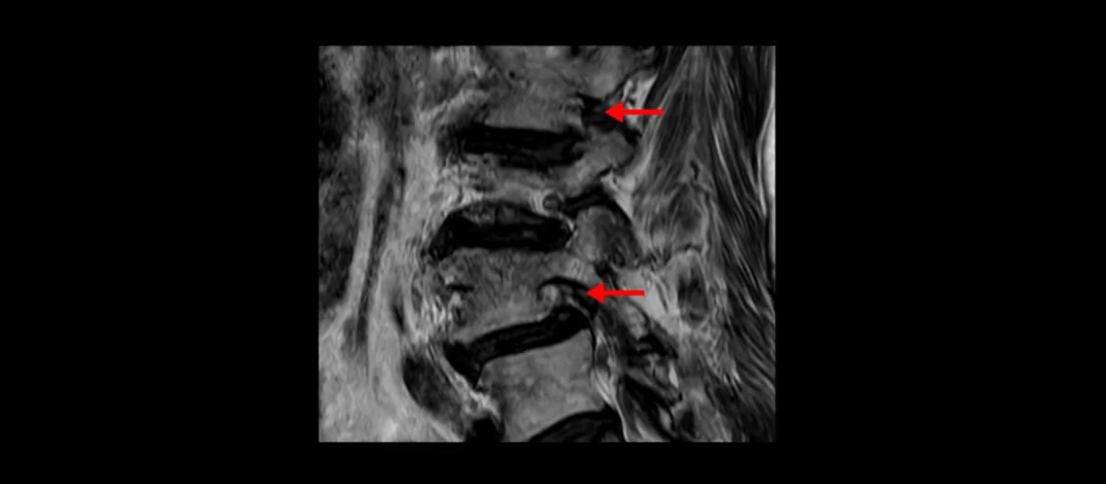

이분 MRI 보시면 허리 3마디의 퇴행이 매우 심합니다.

4번 5번에는 뼈가 밀려 나간 전방전위증도 있고,

또 척추관협착도 매우 심합니다.

척추관이 심하게 좁아져 있습니다.

이렇게 여러 마디가 안 좋고 뼈도 밀려 나가 있으니까 나사박는 수술해야 하는데, 대학병원에서도 수술을 한 번에 못 하고 두 번에 나눠서 해야 한다고 들으셨습니다. 왼쪽으로 신경가지가 빠져나가는 추간공도 많이 좁아져 있습니다.